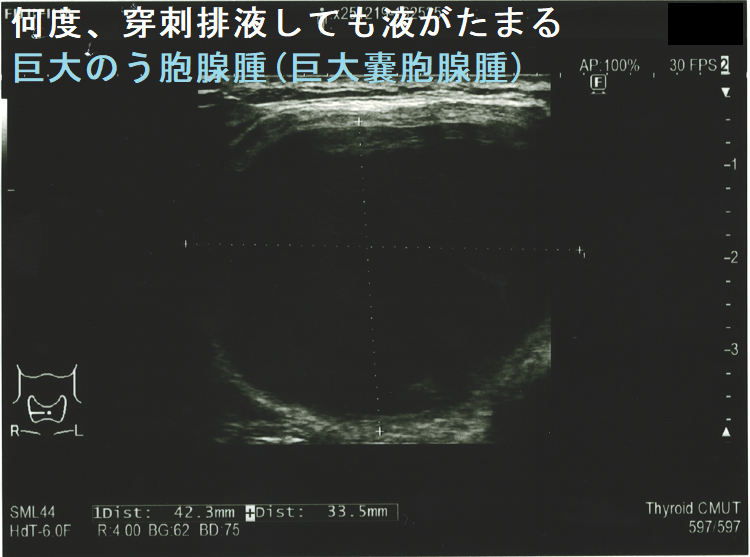

巨大のう胞腺腫(巨大嚢胞腺腫)もしくは通常サイズのう胞腺腫(嚢胞腺腫)が、

には、穿刺排液を行います。しかし、のう胞(嚢胞)中の液体は粘稠なため、通常穿刺針での排液は困難(すぐに詰まってしまう)。太い針でも完全に抜けない事が多い。18G(ゲージ)[輸血用の太い針]を使えば、ほとんどのケースで穿刺排液可能ですが、刺し口から出血して緊急入院になったケースが複数ありました(穿刺時出血)(それ以降、18Gは使用禁止にしました)。18G(ゲージ)でも無理なら、どうしようもありません(海外では16Gの極太針を使用する所もあるようですが・・・)(AJR Am J Roentgenol. 2008 Dec;191(6):1730-3.)。それ以来、無理して太い針を使用せず、抜けない場合は潔く諦めて内分泌外科に甲状腺部分切除(半葉切除が多い)を依頼します。

手術すべきか迷う巨大甲状腺のう胞腺腫(巨大甲状腺嚢胞腺腫)。横径 5.49cmで、ほぼ6cm。80歳以上なら全身麻酔のリスクを冒してまで手術しなくて良いかもしれません。せいぜい次項の経皮的エタノール注入療法(PEIT)ぐらいでしょう。

頻回に穿刺排液しても液がたまる巨大のう胞腺腫(巨大嚢胞腺腫)は、良性腫瘍(のう胞型濾胞腺腫:嚢胞型濾胞腺腫)であっても手術適応になります。単に、のう胞(嚢胞)と呼ばれる事も多いですが、甲状腺組織の破壊・変性によるのう胞変性(嚢胞変性)でなく、れっきとした腫瘍です。

(岩手県立中央病院の報告) 97 x 71 x 60 mmの巨大な甲状腺のう胞腺腫(甲状腺嚢胞腺腫)で、排液後1週間以内に液が再貯留し始めたため、甲状腺半葉切除したそうです。病理標本を確認すると、のう胞周囲は炎症が強く、炎症性浸出液の可能性が考えられました。(第57回 日本甲状腺学会 P2-070 巨大な甲状腺嚢胞により経口摂取困難となった一例)